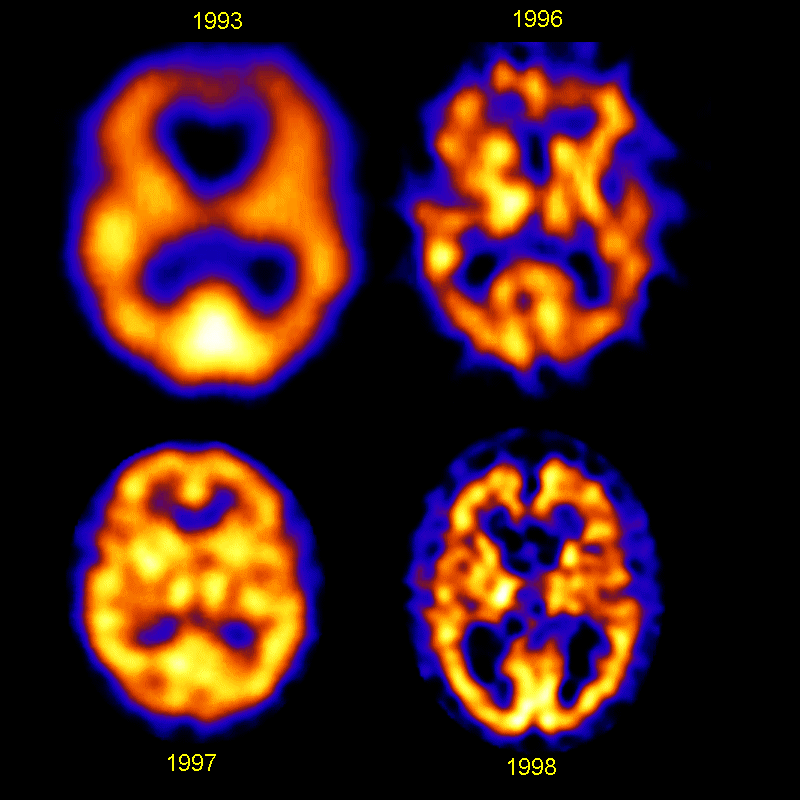

Imagens em falsa cor obtidas com tomógrafo SPECT, mostrando o aumento da resolução obtida com sucessivas gerações de mãquinas, entre 1993 e 1998.